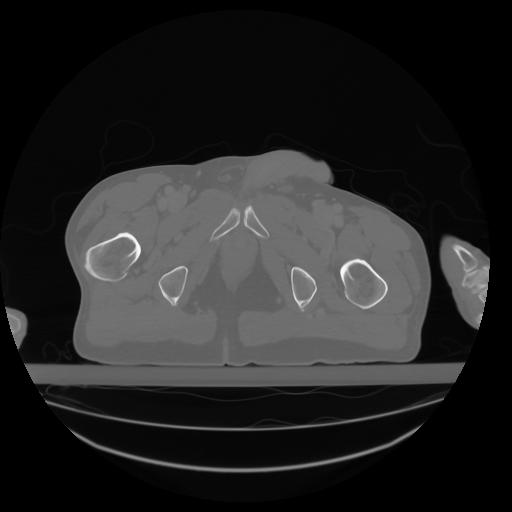

27 CUERPO,CE,Axial,3.0,CUERPO,,